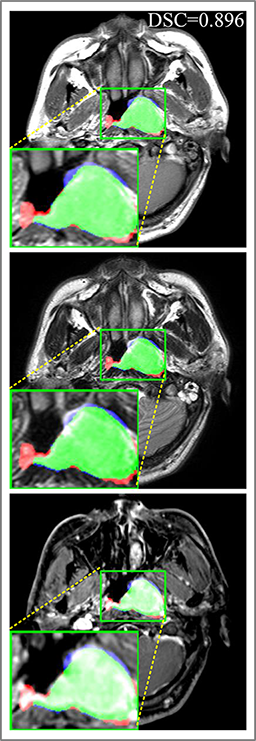

Comparison with ground truth. Some predicted results of MMFNet are shown in 2D images and 3D images in Figure 7 and Figure 8. As shown in these figures, although the shape and size of NPC are varied from each other, MMFNet can still accurately determine the regions of NPC and obtain the accurate contours of tumors. Through analyzing 2D images in figure 7, MMFNet has a capacity to fuse multi-modality MRI to reduce the confusion brought by intensity’ similarity between nearby tissues and NPC. The values of , and of MMFNet are shown in Table 1. MMFNet can reach the best results with , and .

Comparison with related works. Table 1 reports the values of , and for different methods. Predicted masks of different methods are illustrated in Figure 9 and Figure 10, which respectively present results in 2D and 3D images. Through comprehensively analyzing these results, the proposed MMFNet actually have the following properties:

Some typical predicted results of MMFNet are visualized in Figure 12. And it is worth mentioning that our proposed network is extremely time-friendly compared to manually marking by radiologists. Specifically speaking, our proposed method only needs about 9s to realize NPC delineation of a patient, while an experienced radiologist needs 10 to 20 minutes to complete it.